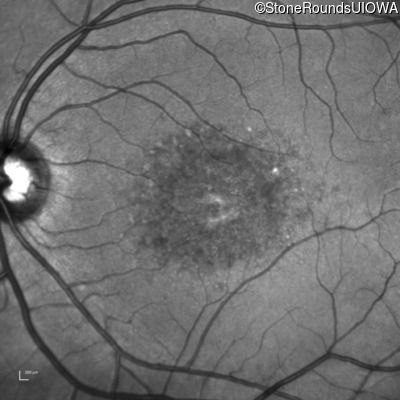

Infrared Fundus Photograph - Right - 10/125 -1

Exemplar